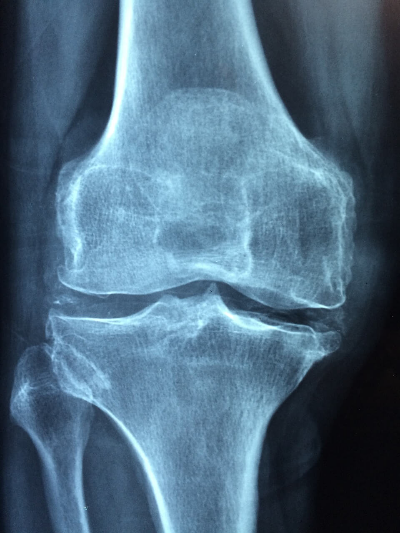

연골연화증 증상

연골연화증은 강도에 따라 다양한 증상이 나타날 수 있으며, 여기에는 다음이 포함될 수 있습니다.

통증과 불편함: 가장 흔한 증상은 무릎 앞쪽의 둔하고 쑤시는 통증입니다.

이러한 통증은 계단 오르기, 달리기, 장시간 앉아있기 등 무릎을 구부리는 활동을 할 때 악화될 수 있습니다.

격자무늬 감각: 일부 사람들은 무릎을 움직일 때 삐걱거리거나 갈리는 듯한 느낌을 받을 수 있으며, 종종 '펑' 또는 '딸깍' 소리가 동반되기도 합니다.

붓기: 슬개골 주위에 염증과 부종이 발생하여 불편함을 일으킬 수 있습니다.

불안정성: 무릎이 "휘어지는" 느낌이나 불안정한 느낌도 연골연화증의 증상일 수 있습니다.